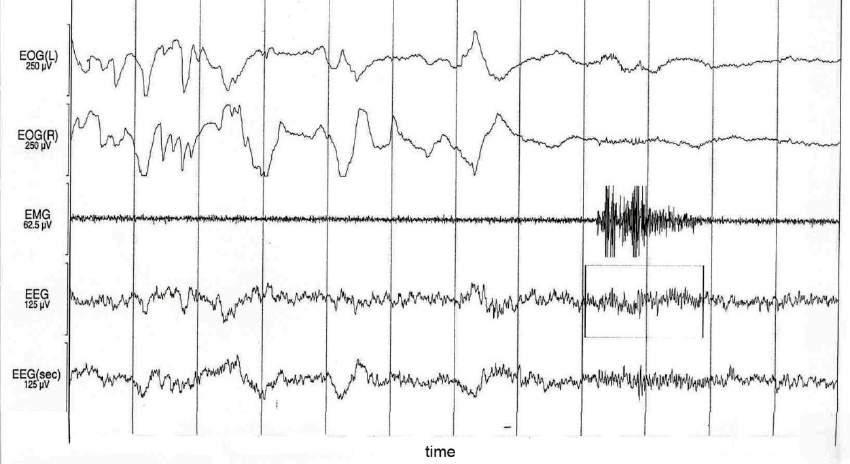

what does this segment show?

• Any abrupt shift in EEG frequency.

• The frequency can be theta, alpha or beta (greater than 16 Hz)

• Arousals cannot be delta waves, K complexes or spindles

• The frequency shift must be greater than or equal to three seconds

• The patient must have greater than or equal to 10 seconds of previous sleep

• REM arousals must have increased chin EMG of greater than or equal to one second (not required for non-REM sleep)

• This is because alpha bursts can be seen during REM sleep and are not pathologic